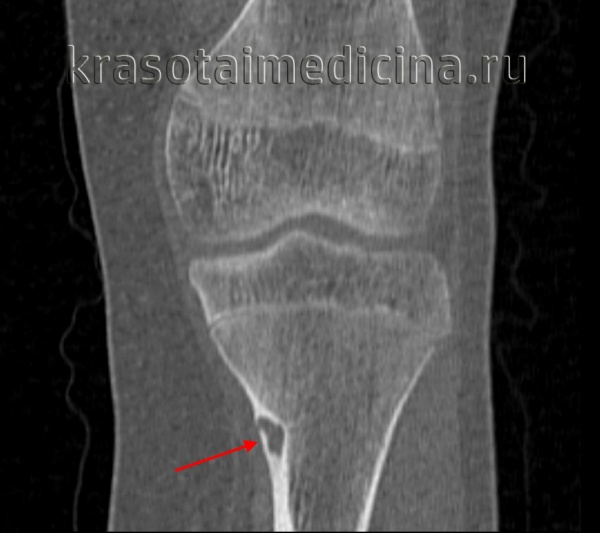

В ходе рентгенологического исследования под кортикальной пластинкой выявляется небольшой округлый участок просветления, окруженный зоной остеосклероза, ширина которой увеличивается по мере прогрессирования заболевания. На начальном этапе определяется четко видимая граница между ободком и центральной зоной остеомы. В последующем эта граница стирается, так как опухоль подвергается обызвествлению.

При гистологическом исследовании остеоидной остеомы обнаруживается остеогенная ткань с большим количеством сосудов. Центральная часть остеомы представляет собой участки образования и разрушения кости с причудливо переплетающимися балочками и тяжами. В зрелых опухолях выявляются очаги склерозирования, а в «старых» - участки настоящей волокнистой кости.

Диагноз выставляется на основании данных рентгенографии и / или компьютерной томографии. При изучении рентгеновских снимков нужно учитывать, что реальный размер экзостоза не соответствует данным рентгенограммы, поскольку верхний, хрящевой слой на снимках не отображается. При этом толщина такого слоя (особенно у детей) может достигать нескольких сантиметров.